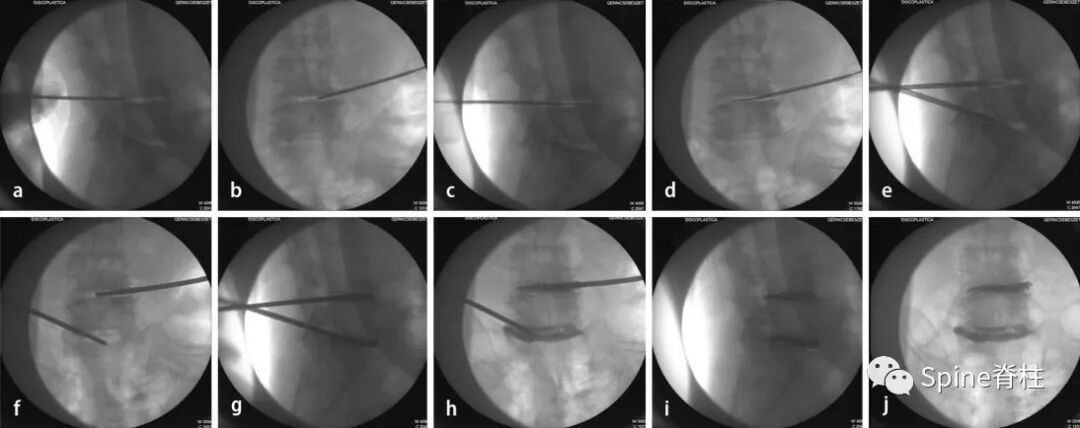

图: PCD术中图像a: 向椎间盘间隙插入Jamshidi 针; b: 针在正位时的位置; c,d: 将K-wire 插入Jamshidi针内; e,f: 插入椎体成形术套管针; g,h:PMMA骨水泥填充椎间盘; i,j: 术后情况